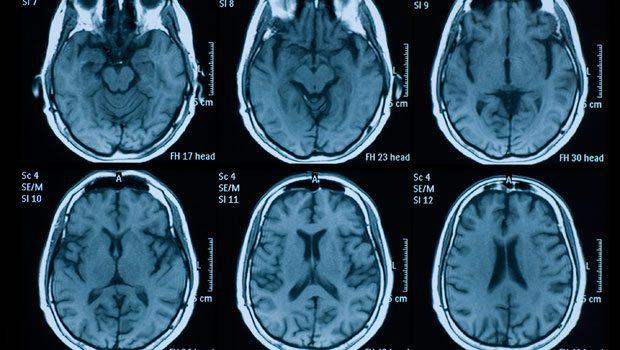

Cinsiyyətini dəyişən qızın beyin rentgeni həkimləri təəccübləndirib.

Vyana alimlərinin araşdırmasına görə, cinsiyyətini dəyişəndən sonra testesteron hormon verilən gənc qızın beyninin quruluşu da dəyişib. O, artıq qadınlar kimi bir neçə işi eyni anda görə bilmir. Bundan başqa, onun beyninin dil və ünsiyyəti təmin edən hissəsində də zəiflik müşahidə edilir.

Alimlərin açıqlamalarında bildiriblər ki, 18 yaşlı transseksual gəncə 4 həftə boyunca testesteron hormonu verilib və onda bu dəyişikliklər baş verib.

"Gəncin beynindəki bu dəyişikliyin gözlənilən idi. Testesteronun təsirindən beyində dəyişikliklər olacağını təxmin edirdik. Aparılan müayinələr isə bu ehtimalları təsdiqləmiş oldu. Nəticə, cinsiyyət hormonu ilə beynin əlaqəsini təsdiqləmiş oldu", - deyə alimlər bildiriblər./milli